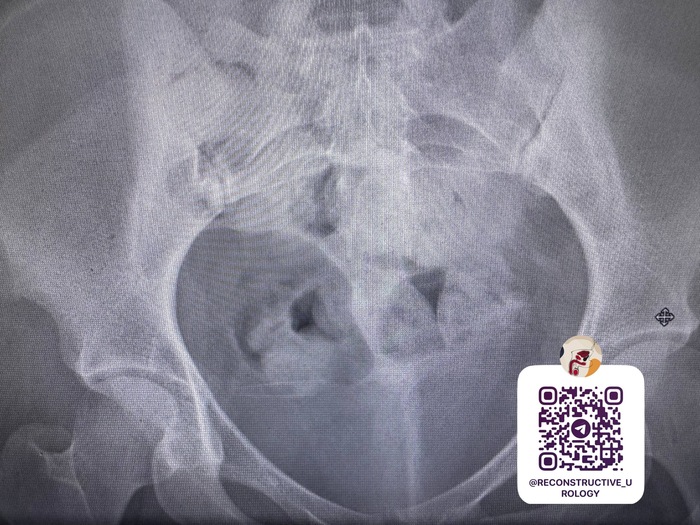

Что у меня — РМЖ, 2ст, опухоль располагается там, откуда начинает расти титечка, недалеко от подмышки, размер 1.2*1.5 до химозы, но была круглым шариком, после размеры по +0.2, но она плоская и по узи распалась на неоднородную структуру, был метастаз в подмышечный лимфоузел. Локация прям под кожей и невооруженным взглядом ее было видно. Изначально это была доброкачественная опухоль, типа фиброаденомы (узи от апреля), в начале лета я словила охуенную аллергию на два месяца и, как я думаю, она то и сыграла роль в этой неприятной истории. В июне я пошла на повторное узи, где меня почти похоронили загробным голосом (пост есть ниже), ну и пошла поехала вся круговерть с диагнозом, биопсией и проч.

2 ЭТАП: операция. Тут самое интересное, потому что изначально я шла на резекцию (удаление самой опухоли + лимфоузлы + немного соседних тканей), с мыслью, что как все закончится, я пойду на пластику и сделаю все красиво НО, как оказалось, титюхи у меня маленькие и резекцию потом ни один хирург от бога не исправит, будет некрасиво + нихуевый шанс что-то упустить во время операции и вернуться через пару лет за добавкой. Спасибо боженьке, что послал мне дотошного дядьку-онколога, который, что называется «сам себе в зеркало не улыбаюсь», он пересматривал мои узи, всю перетрогал, переделал узи дважды и подвел меня к мысли о мастэ, но с сохранением соска и ореолы, ткскзт и ему хорошо, он все что надо уберет и мне приятно, что сисечка красивая будет. На том и порешали.